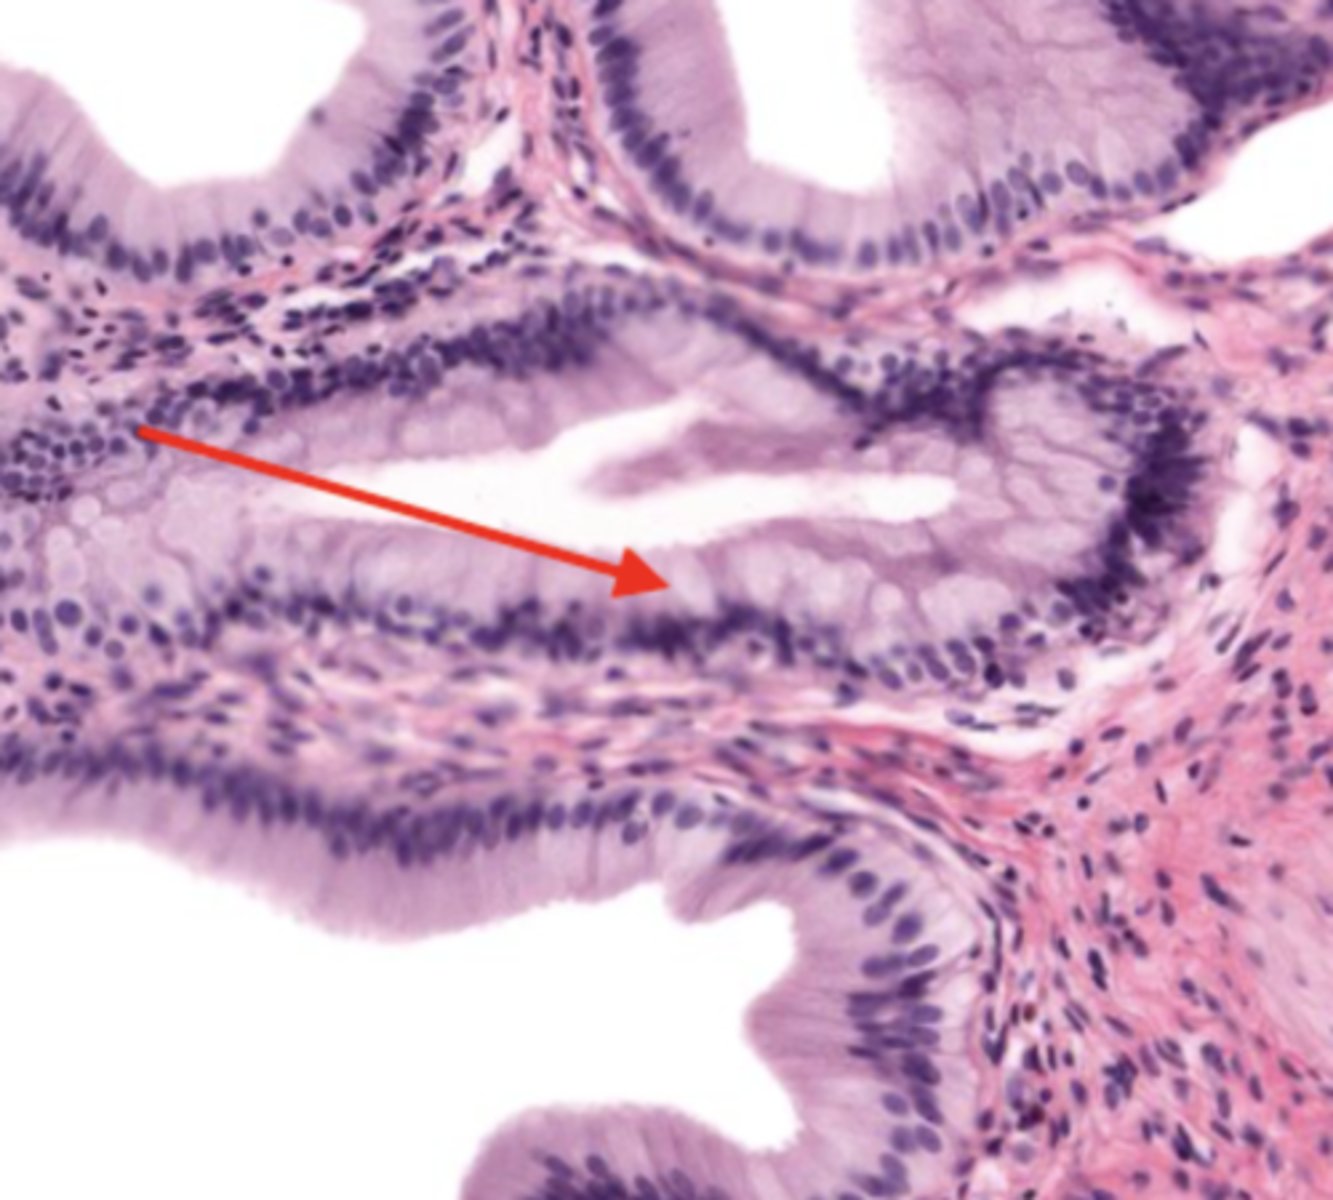

villi (jejunum)

intestinal crypts (jejunum)

mucosa (jejunum)

mucosal epithelium (jejunum)

lamina propria (jejunum)

muscularis mucosa (jejunum)